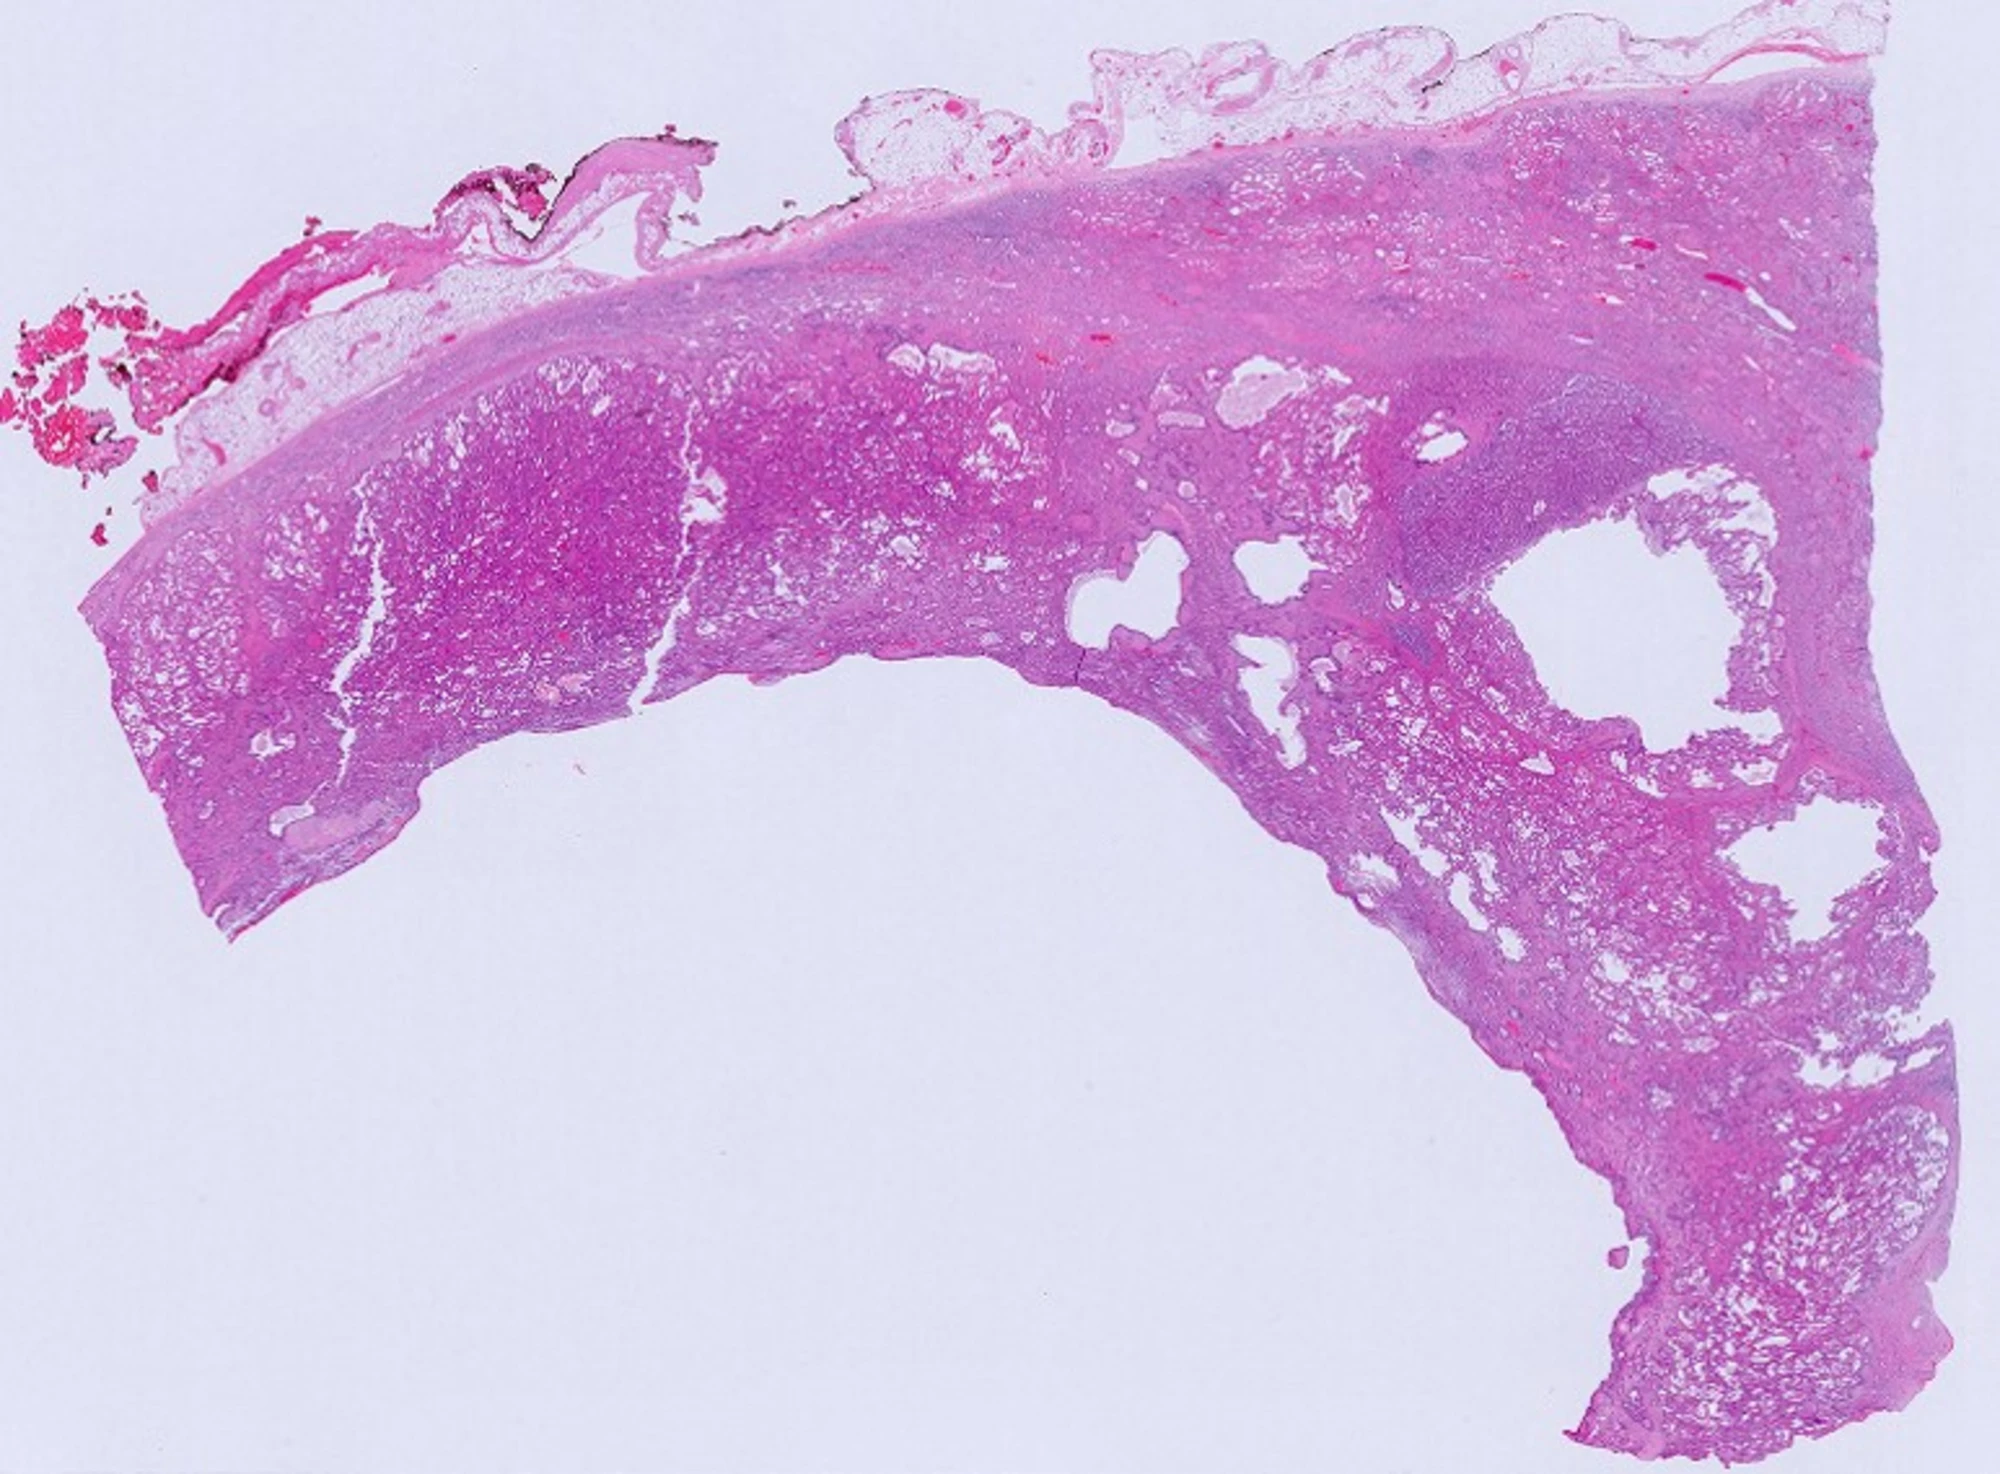

A 40 year old male with a history of focal segmental glomerulosclerosis (diagnosed at 15 years of age) complicated by end-stage renal disease presented with abdominal pain after peritoneal dialysis. MRI abdomen without contrast showed 2.6 cm x 3.6 cm complex cystic mass in interpolar right kidney and and 1.9 cm x 1.6 cm complex cystic mass in lateral mid to lower pole of left kidney. Patient subsequently underwent bilateral radical nephrectomy.

What is the most likely diagnosis?

- Acquired cystic disease-associated renal cell carcinoma